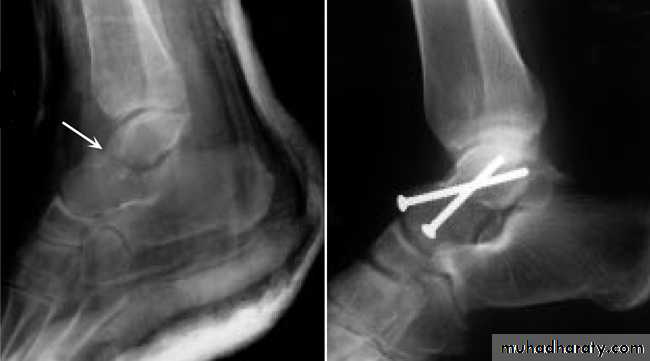

Fracture Talus: A talus fracture is a break in one of the bones that forms the ankle. This type of fracture often occurs during a high-energy event, such as a car collision or a high-velocity fall. Because the talus is important for ankle movement, a fracture often results in significant loss of motion and function. In addition, a talus fracture that does not heal properly can lead to serious complications, including chronic pain. For this reason, many talus fractures require surgery.